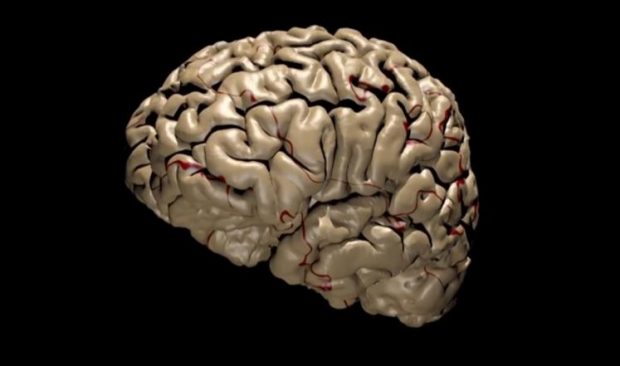

حذرت دراسة فنلندية حديثة من تناول الخمور لتأثيرها على تطور بنية الدماغ البشري خلال فترة المراهقة والشباب.

وأظهرت الدراسة أن شرب الخمر يؤثر على بنية الدماغ عبر تقليص حجم المناطق الرمادية فيه، كما يؤثر على تشكيل “القشرة الحزامية الأمامية”.